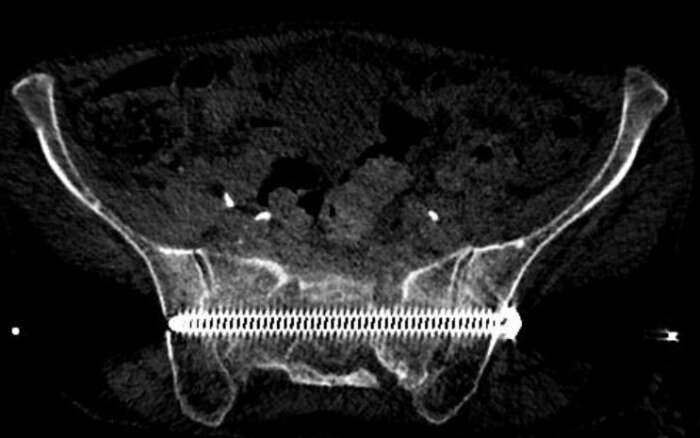

In diesem Beispiel war die Patientin vier Wochen nach einem Sturz nur noch mit Krücken und mit Schmerzen mobil. Die Computer Tomographie (CT) zeigte einen nicht verschobenen Bruch des Kreuzbeins und eine leicht verschobene Fraktur des Schambeins. Während der Operation implantierten wir CT-gesteuert zwei 7,3-mm-Schrauben. Die Schrauben gingen durch beide Ilio-Sakralgelenke und erste und zweite sakrale Wirbelkörper. Die Patientin konnte am nächsten Tag nach Hause entlassen werden und war schmerzfrei mobil.

Implantation einer 7.3 mm Schraube quer durch das Kreuzbein. Die Rückenmarks-Nerven können Millimetergenau geschont werden